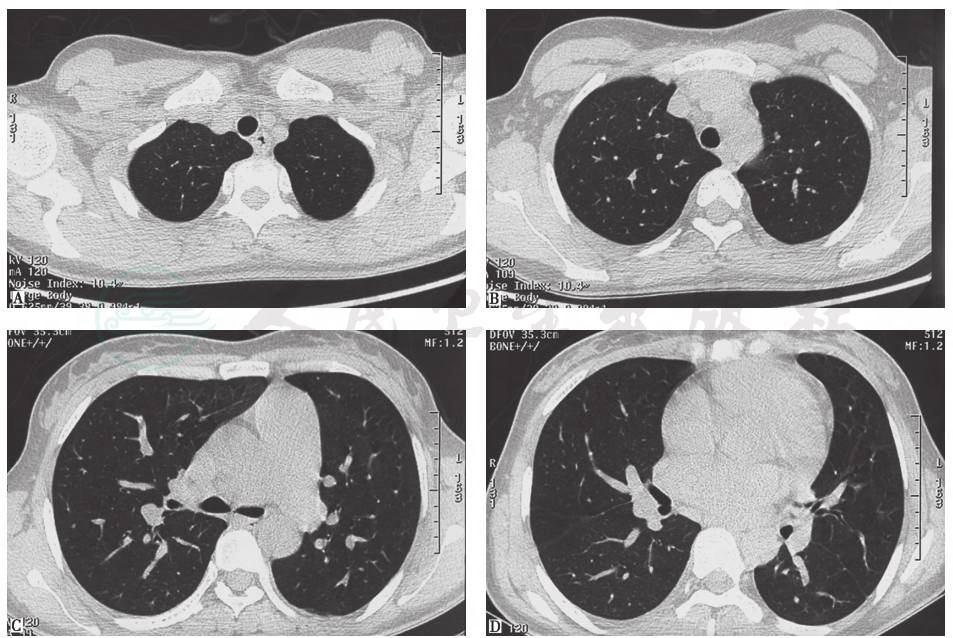

胸部CT(2015年1月6日):双肺多发高密度影,右下肺明显,双侧少量胸腔积液,肺动脉增宽,纵隔未见肿大淋巴结影(图3)。

图3 胸部CT表现(2015-01-06)

胸部CT(2015年1月23日):双肺内散在斑片状高密度影较前有所吸收,右肺下叶斑片影可见小空洞形成,双侧胸腔积液吸收、好转(图4)。

图4 胸部CT表现(2015-01-23)